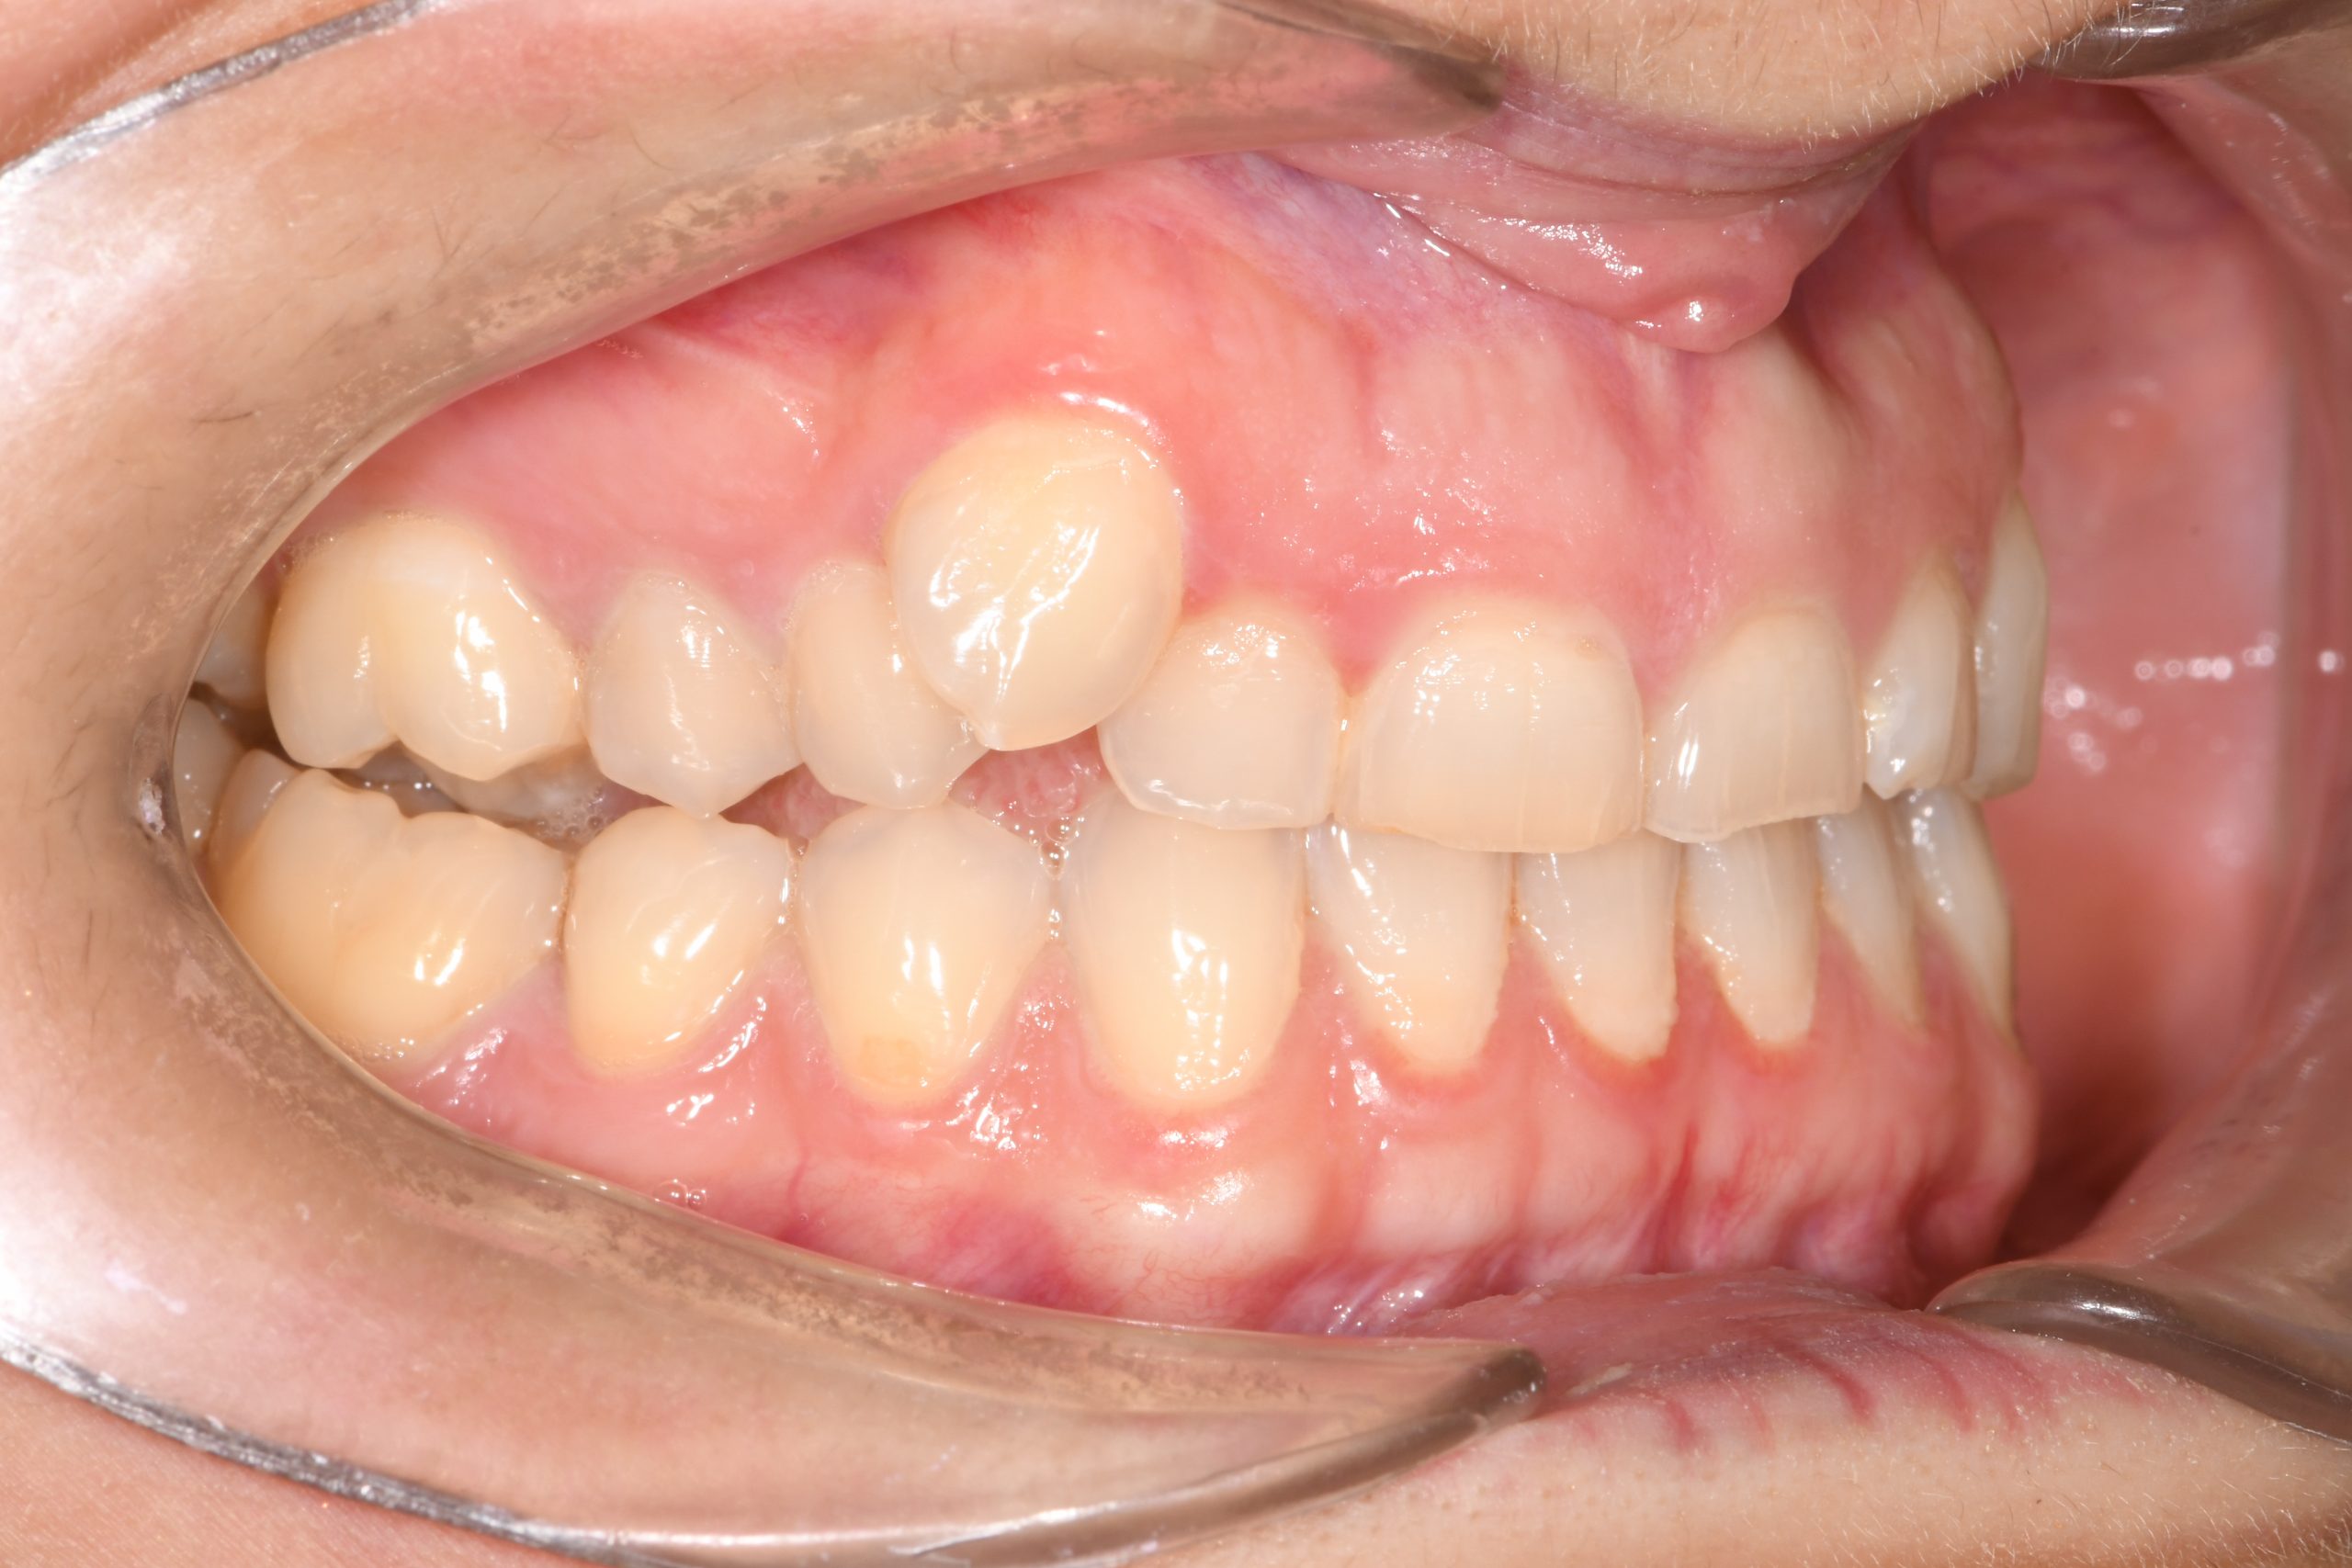

Az elmúlt évekből rengeteg szakmai referenciát tudnánk bemutatni, amelyek különböző fogszabályozási problémákat oldottak meg. Válogatva a több száz esetből, ezen az oldalon olyan képeket, információkat igyekeztünk bemutatni, amelyeknek a segítségével a jövőbeni pácienseinknek azt tudjuk üzenni: A Te fogsorod is lehet gyönyörű!

(Képeket a Pácienseink külön írásos beleegyezésével mutatjuk be!)